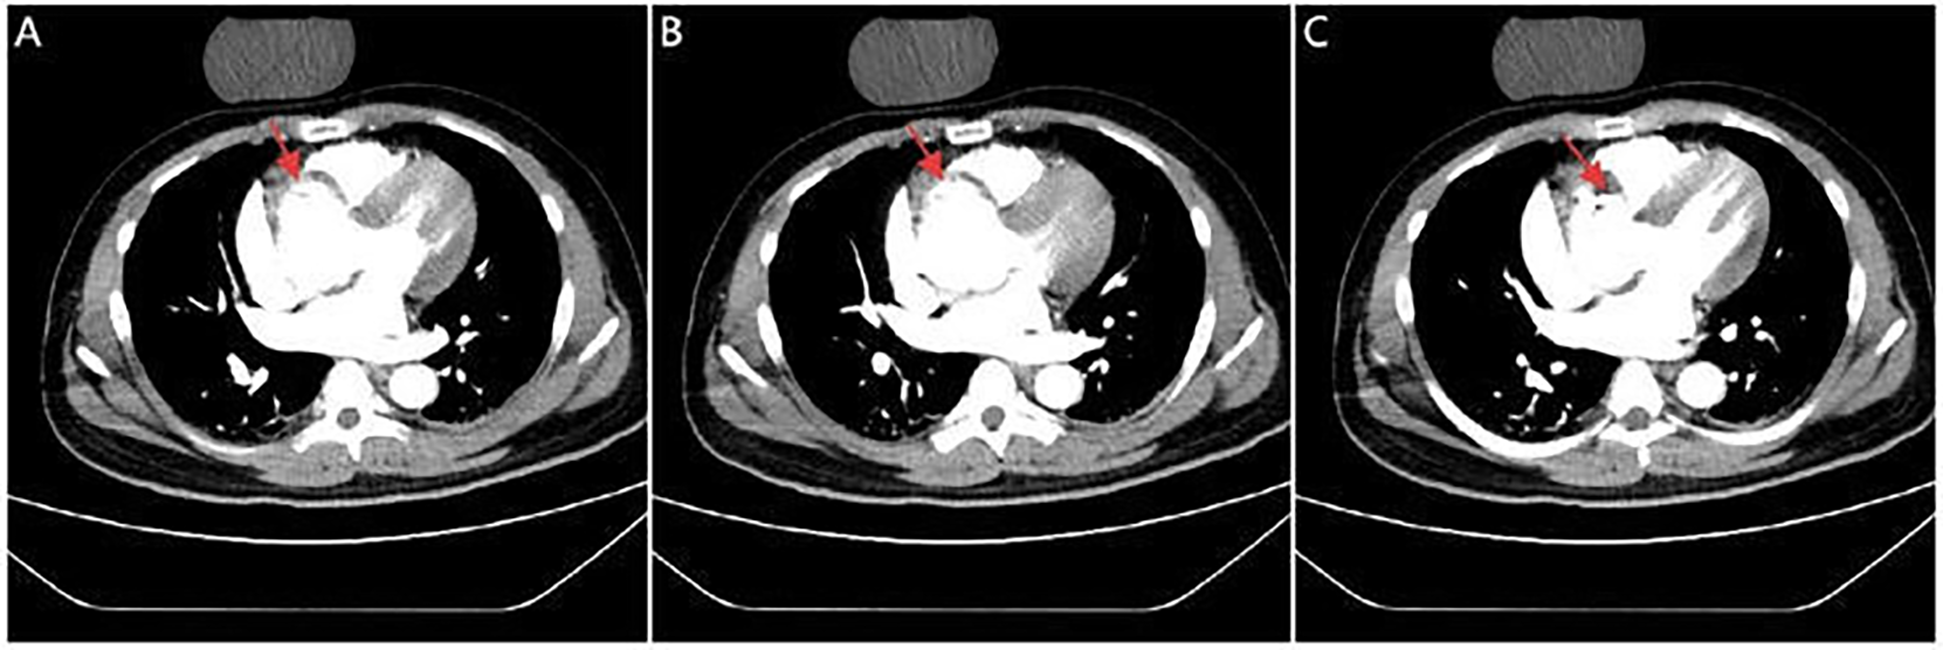

A 42-year-old man with no known comorbidities and a family history of AD presented with sudden-onset chest pain during esports gameplay. ECG showed inferior STEMI with complete heart block (Figure 1A). CAG revealed a normal left coronary system, but the RCA could not be engaged. Aortic root angiography showed no anomalous origin of the RCA; however, it suggested a possible dissection of the right SOV (Figures 1B–D; Supplementary Video 1). CTA revealed ascending aortic dilation and a localized dissection of the right SOV (Figures 2A–C; Supplementary Video 2). The emergency transthoracic echocardiography (TTE) revealed dilation of the ascending aorta, measuring 43 mm in diameter. Despite the recommendation for immediate surgery, family hesitation delayed intervention. The operative findings showed that a dissection of SOV extending into the RCA ostium. Coronary artery bypass grafting (CABG) and sinus reconstruction were performed, however the patient developed cardiogenic shock and refractory ventricular arrhythmias. The family declined mechanical circulatory support (MCS), and the patient subsequently died.

Figure 2

CTA images. Serial CTA images (A–C) show located right coronary sinus of valsava dissection (red arrow).